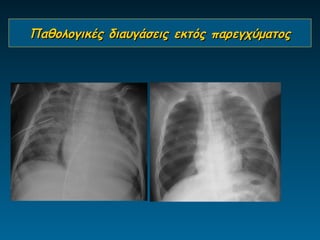

Παθολογικές διαυγάσεις εκτός παρεγχύματος

Διαφυγές αέρα